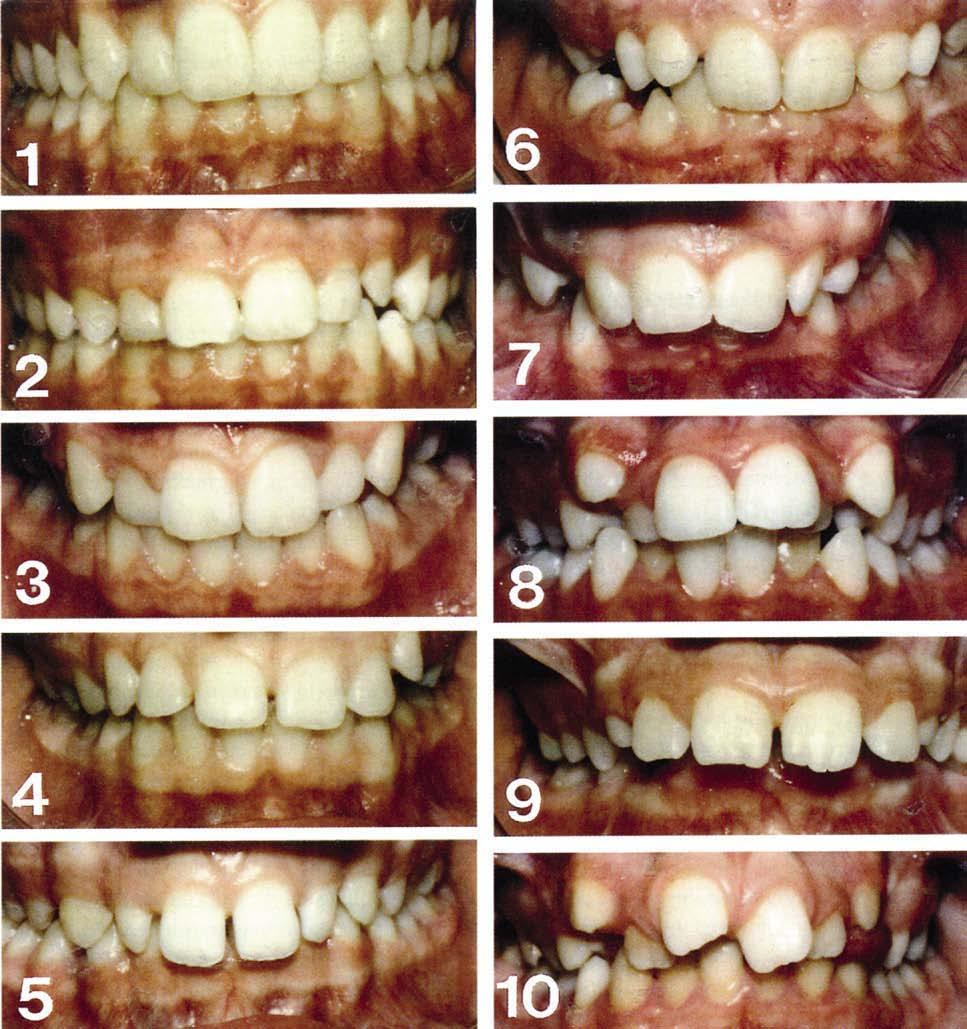

Aesthetic Component

This records the aesthetic handicapping of the malocclusion and is based on a series of ten photographs, which show a graduated decrease in dental aesthetics (Fig. 1.20). A score is given from 0 to 10 based upon the perceived aesthetic impairment of an individual’s malocclusion, not morphological similarities with the photographs. A highlevel agreement has been found between scores given by professionals and those given by patients.

Figure 1.20 The aesthetic component of the IOTN. The SCAN scale was first published in 1987 by the European Orthodontic Society (Evans R and Shaw W, Preliminary evaluation of an illustrated scale for dental attractiveness. Eur J Orthod 9: 314–318). IOTN aesthetic and dental health components reproduced courtesy of Orthocare.